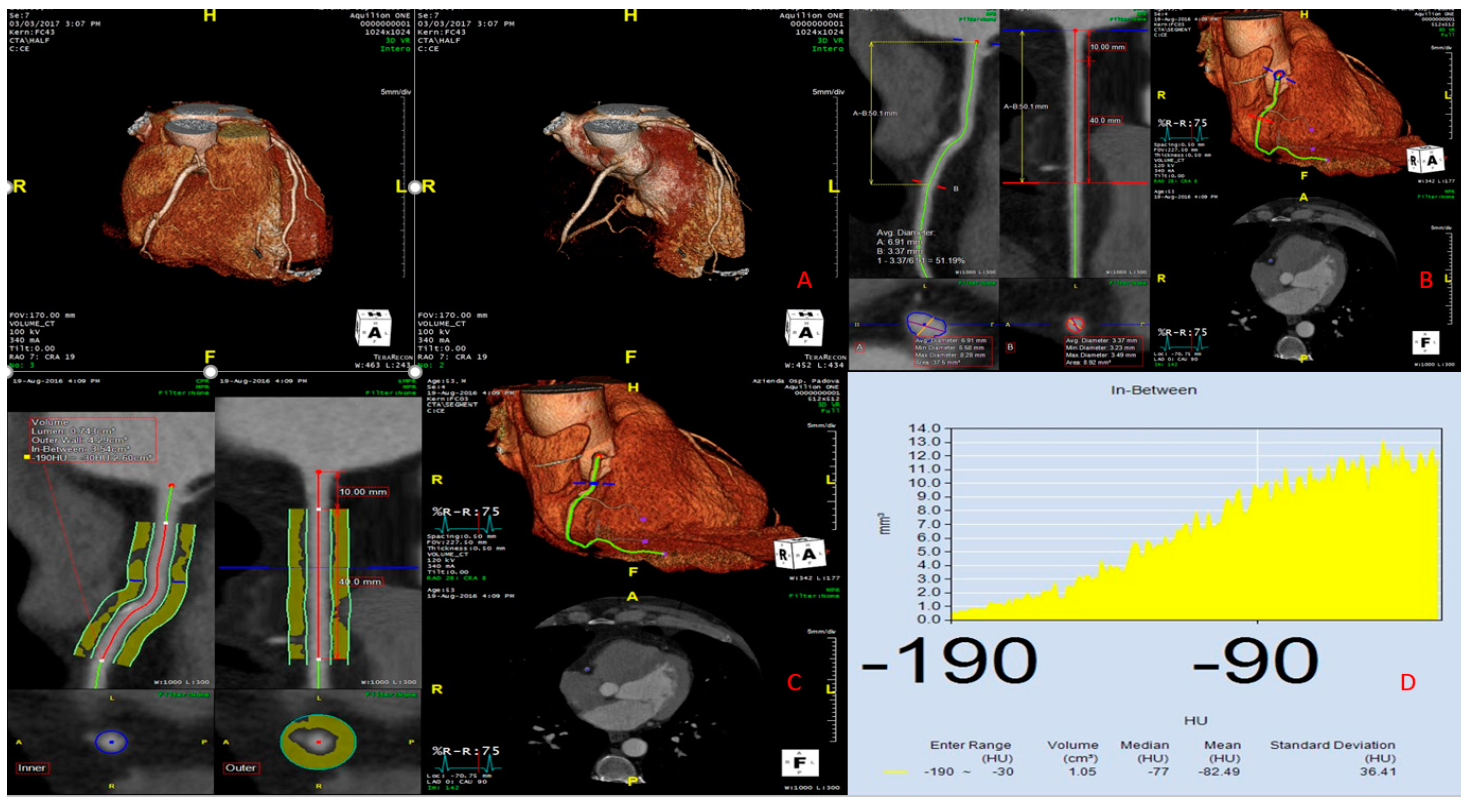

| CT Analysis and pFAI Values | ||||||

| Coronary arteries with no lesions | 1 (6.7%) | 6 (42.9%) | 2 (22.2%) | 9 (23.7%) | 12 (100%) | <0.001 |

| Diameter (mm) | 3.32 ± 0.69 | 3.46 ± 0.91 | 2.79 ± 0.66 | 3.26 ± 0.79 | 3.80 ± 0.88 | 0.5473 |

| Volume (cm3) | 1.20 ± 0.80 | 1.38 ± 0.65 | 1.02 ± 0.41 | 1.23 ± 0.68 | 1.74 ± 0.56 | 0.090 |

| Median (HU) | −82.00 ± 13.14 | −80.62 ± 14.92 | −80.00 ± 13.59 | −81.19 ± 13.52 | −93.33 ± 7.92 | 0.041 |

| Mean (HU) | −86.45 ± 11.69 | −84.63 ± 13.88 | −84.79 ± 13.78 | −85.51 ± 12.47 | −96.02 ± 6.66 | 0.0077 |

| Standard deviation (HU) | 37.01 ± 5.20 | 35.28 ± 7.04 | 36.53 ± 8.47 | 36.24 ± 6.34 | 40.02 ± 2.64 | 0.025 |